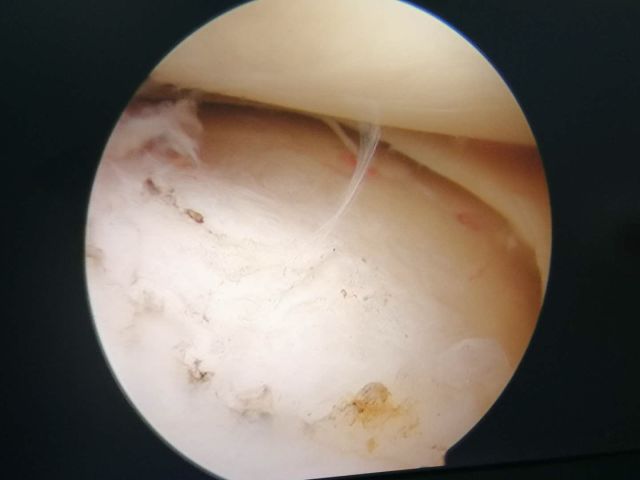

这是参加手术的陈文锋医师拍摄的一张手术切口的照片。沈主任就是借由这几个不到半厘米的小口,就完成了骨折部位的精准复位和内固定。

细小的手术切口